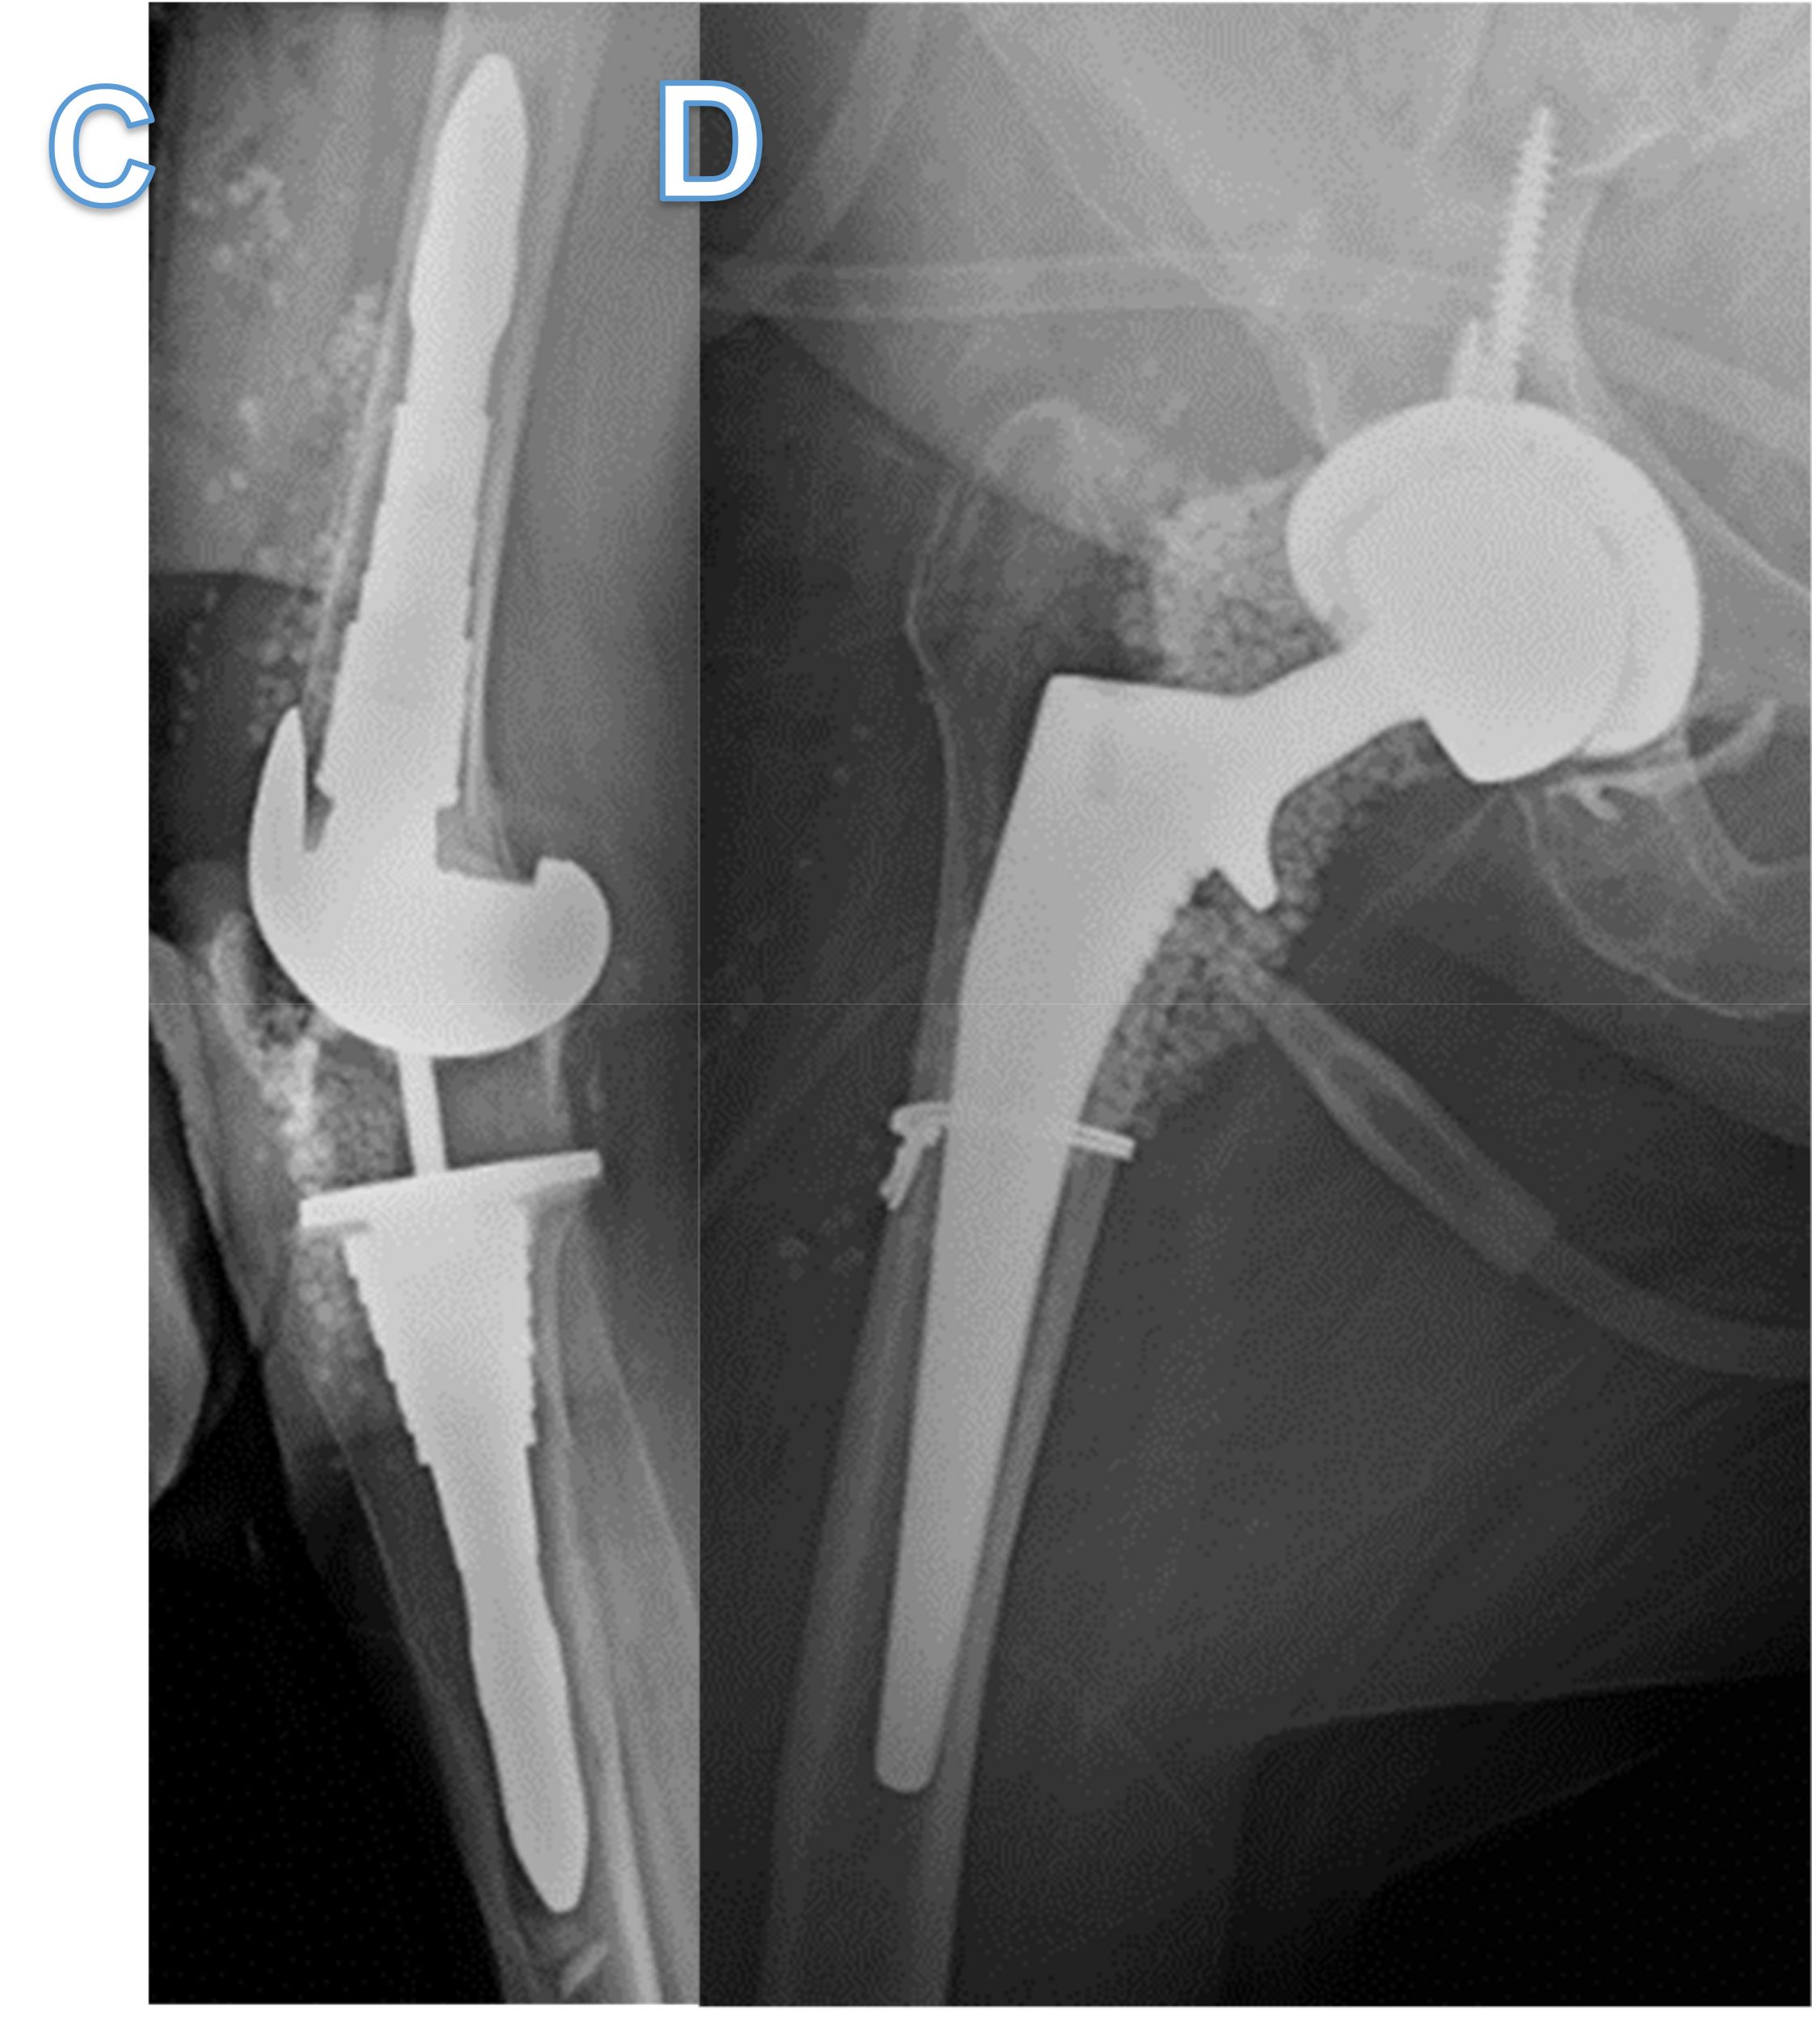

Figure 2.

Timeline of the patient’s recalcitrant MRSA PJI of knee and hip. Red steps indicate continued infection, while green steps indicate resolution of infection as seen with no clinical symptoms and sterile deep tissue bacteriological cultures. The figure shows it was not until bacteriophage therapy was used that cure of infection occurred. IA refers to intraarticular administration. DAIR refers to debridement and implant retention surgery. MSIS refers to musculoskeletal infection society. The MSIS criteria for PJI diagnosis are well documented elsewhere [2].

When two-stage revision surgery fails to cure PJIs, evaluating the reason for such a failure is paramount to eradicating the infection. Common risk factors for failure include obesity, immunosuppression, poor wound healing and uncontrolled infections at other sites, such as endovascular infections [7]. Furthermore, poorly treated PJIs with inadequate source control can lead to uncontrolled planktonic infections presenting with recurrence of symptoms soon after the removal of the prosthesis. In this case, the patient had no risk factors for failure, nor did she have a distal source of infection, as demonstrated by no endocarditis on transesophageal echocardiogram or any niduses of MRSA infections on CT scans of the chest, abdomen and pelvis. In addition, her initial improvement on antibiotics supported adequate source control and eradication of her planktonic MRSA infection. However, within weeks of stopping antibiotics, her PJIs would recur with the same MRSA, indicating that a deep-seated recalcitrant infection was present that conventional antibiotics could not eradicate (Figure 2).